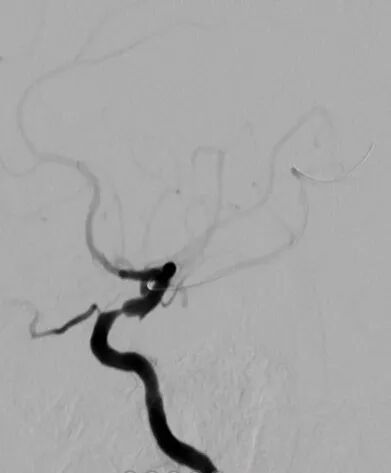

术后影像及检查

影像结论:术后残余狭窄小于 10%。

导丝怎么扩【载药时代 球扩天下】NOVA DES®颅内药物洗脱支架在颈内动脉颅内段重度狭窄中的应用体会二例!_https://www.jmylbn.com_新闻资讯_第30张

手术总结

操作体会

颅内球扩支架是主要适应于血管相对较短、较直的血管,同时无明显穿支动脉;术中微导丝远端放置需格外小心,可以考虑塑回形圈,避免前置或支撑不佳;相对于分支较少的粥样硬化狭窄患者,赛诺神畅 NOVA DES®内药物洗脱支架顺应性及支撑效果均为上佳选择。同时赛诺神畅 NOVA DES®内药物洗脱支架术后解剖影像复位较颅内自膨支架好。术后进行复查随访,与APOLLO支架以及颅内自膨支架再狭窄率进行对比。